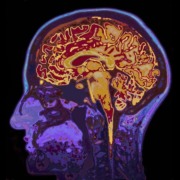

Eine britische Studie kam zu dem Ergebnis, dass eine schwere Corona-Infektion das Gehirn langfristig schädigen kann. Die Forscher stellten fest, dass viele COVID-Patienten noch 12 bis 18 Monate nach einem Krankenhausaufenthalt schlechtere kognitive Leistungen aufwiesen als gesunde Vergleichspersonen.

Scans zeigten eine Reduktion des Gehirnvolumens in bestimmten Bereichen.

Die kognitiven Defizite waren mit einer Alterung des Gehirns um 20 Jahre vergleichbar.